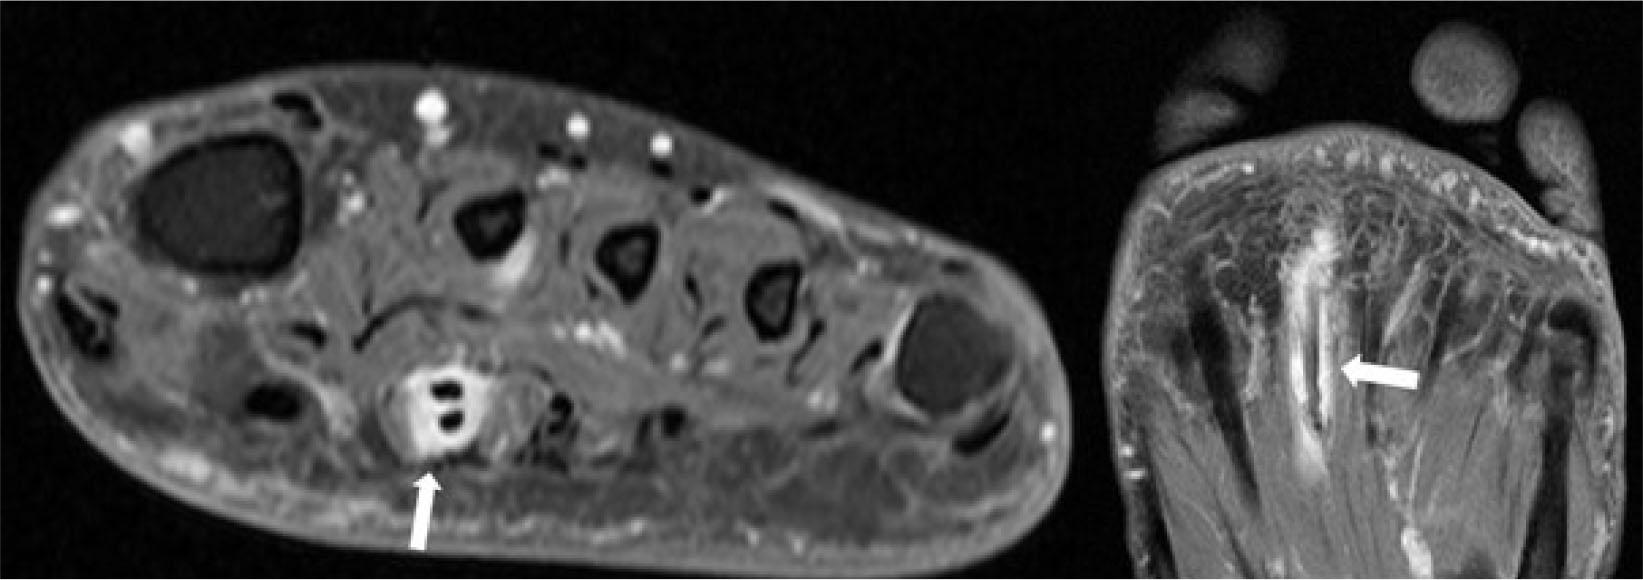

Chopart’s injury usually occurs from a midfoot inversion injury (‘midfoot sprain’), often in conjunction with a lateral ankle ligament tear. Tears, often accompanied by small bony avulsions, occur at the dorsal calcaneocuboid, bifurcate, and dorsal talonavicular ligaments (Fig. 6)(6). US is an effective screening examination for such injuries(6), and a combination of radiographs and US usually provides sufficient assessment for clinical management. CT and MRI enable a fuller assessment if clinically warranted as in, for example, high-performance athletes (Fig. 6). CT readily depicts the full range of avulsion fractures, while MRI may reveal concomitant variable BME as a feature of disease activity.

Fig. 6.

48-year-old woman with midfoot sprain. Longitudinal greyscale US images of Index Choparts joint show A. moderate severity swelling indicative of sprain of the dorsal talonavicular ligament (arrowheads) between the talar head (TAL) and the navicular bone (NAV) and B. severe tear of the dorsal calcaneocuboid ligament (arrowheads) with avulsion fractures (arrows) from the calcaneum (CAL) and cuboid (CUB) bones. US also showed additional avulsion fractures and a moderate-severity anterior talofibular ligament tear (not shown). Corresponding CT with C, D. sagittal and E, F. axial reconstructions shows several small calcaneal (CAL) and cuboid (CUB) avulsion fractures (arrows)